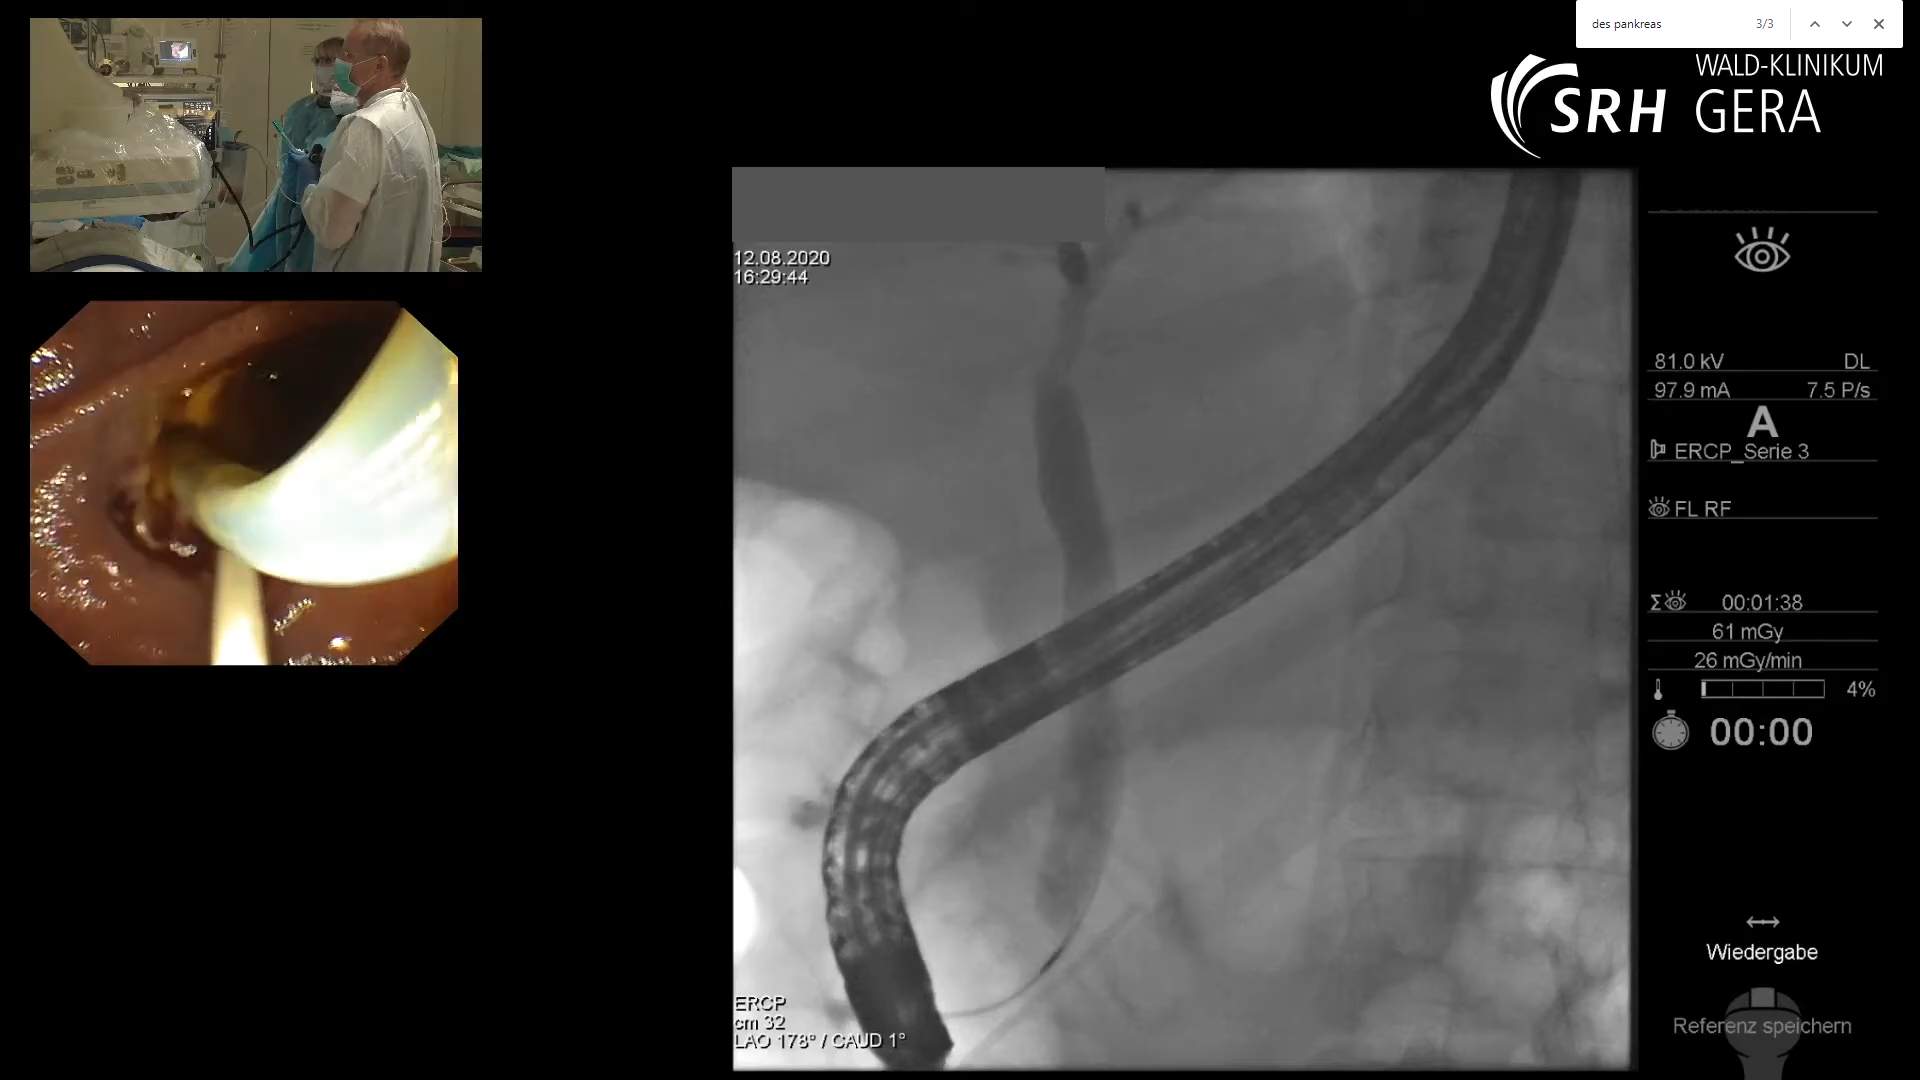

From www.eusandmore.de

ERCP mit Precut, Papillotomie, Steinextraktion und Einlage eines What Is Ercp Stent endoscopic retrograde cholangiopancreatography (ercp) is a procedure that combines upper gastrointestinal (gi). endoscopic retrograde cholangiopancreatography (ercp) is an invasive procedure used for the diagnosis and treatment. Endoscopic retrograde cholangiopancreatography, or ercp, is a procedure to diagnose and treat problems in the liver, gallbladder,. These are hollow tubes, made from plastic or metal alloys, that help with drainage of. What Is Ercp Stent.